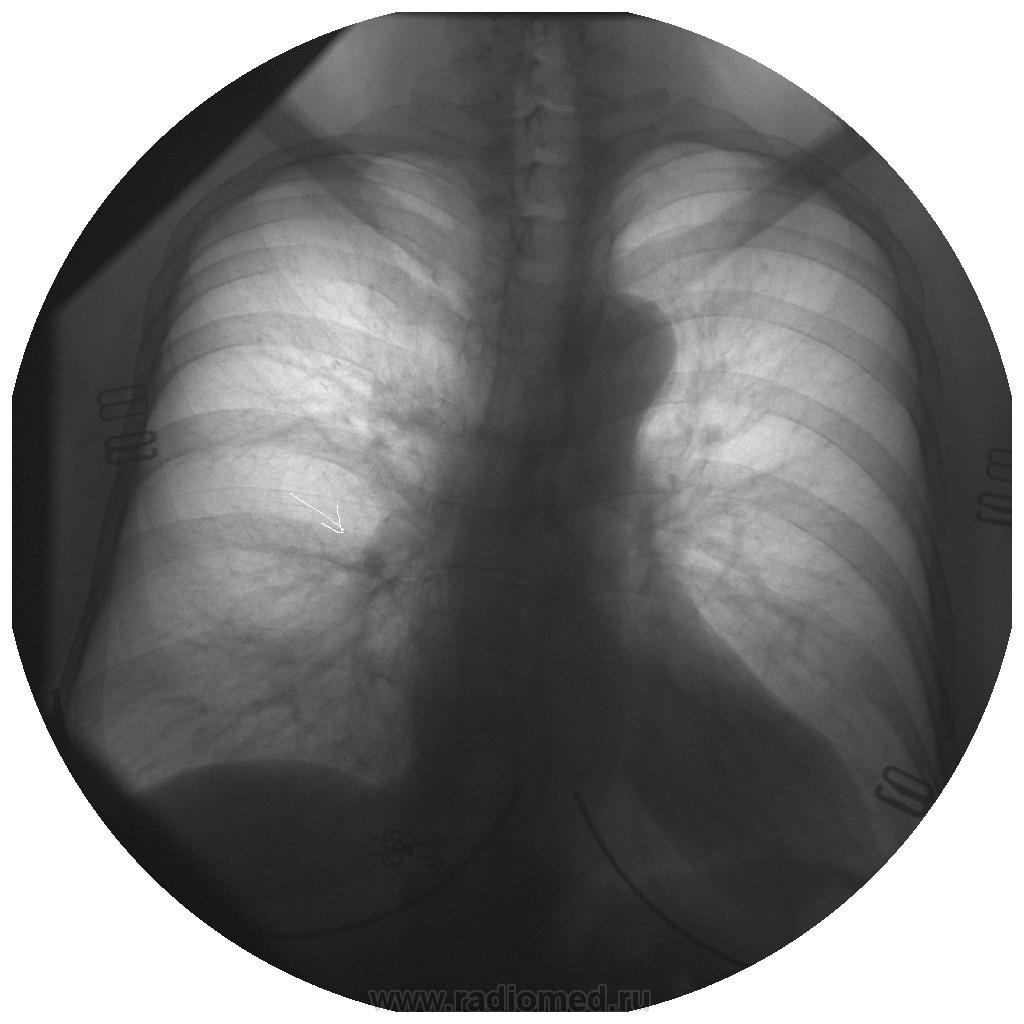

Уважаемые коллеги! Хотелось бы Вашего мнения. R-гр. ОГК в 2 проекциях - в правом корне доп. тень? Да, и прошу не удивляться "круглым" снимкам - вот так снимают у нас...

Бронхопульмональный лимфатический узел.

Мой вариант - сосуд в ортопроекции. И, опять-таки, на мой взгляд, на снимках в прямой и боковой проекциях указаны разные отделы.

Сосуд в ортопроекции.

Да, по прямой, ортоград...А вот то что на боковой, так то нуждается минимум в линеечке.

Согласен с сосудом. И на прямой он. И на боковой. Тоже он - сосуд. Но уже другой!) Посмотрите по взаиморасположению - относительно пространственных ориентиров - той же аорты (верхнего края дуги) - сосуд так интересно не меняет своё местонахождение, пусть и при различном объёме воздуха у пациента в груди.

Эта цифровая рентгенография - беспленочная; снимки моментально попадают в память компьютера, здесь же и диагностируем, в смысле с экрана монитора. Да, кстати, мои снимки позитивные - это я их инвертировал прежде, чем опубликовал.

Ну а почему "круглые" - откровенно говоря, эта цифровая рентгенография  - прицельная, поэтому просил не удивляться им в начале ветки. smiley Хотя есть возможность делать обзорные на кассеты, но пока нет оцифровщика...